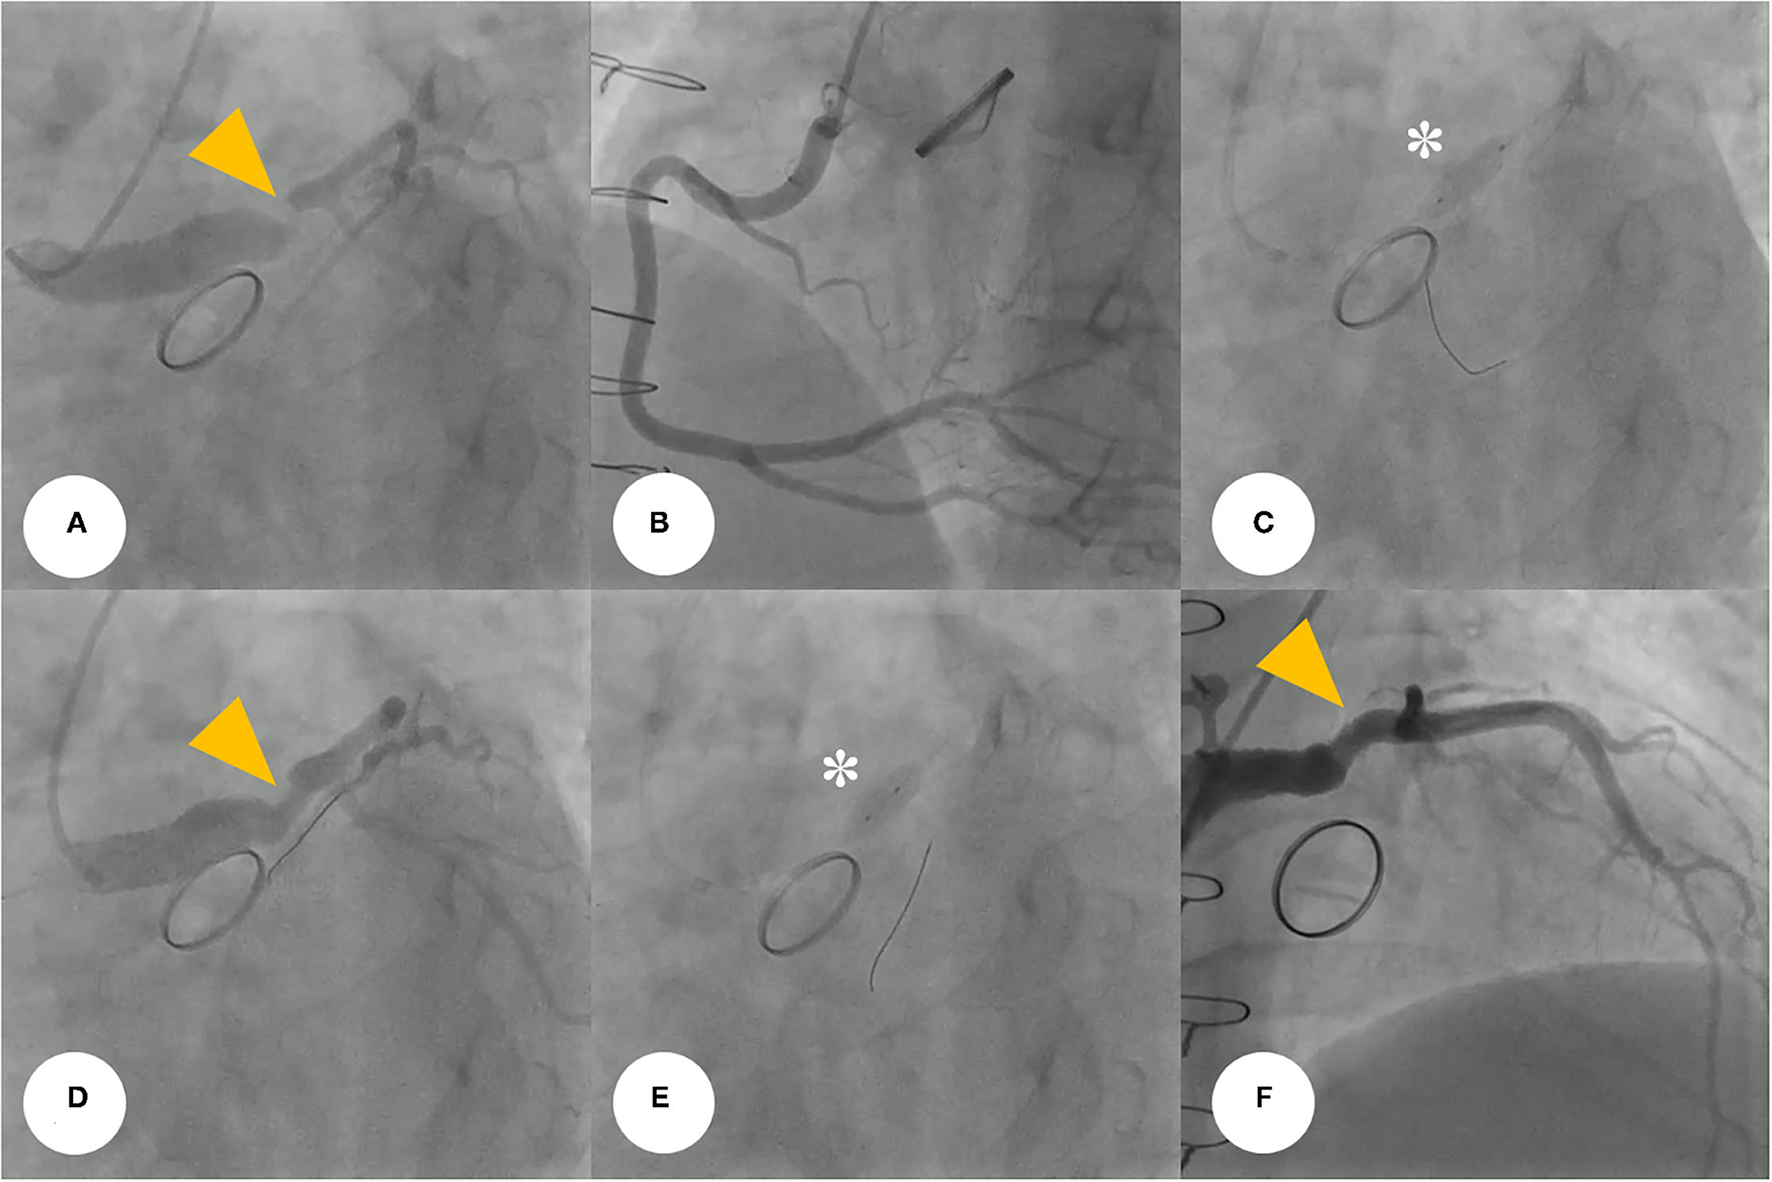

Figure 4

(A) Coronary angiogram demonstrates severe post-anastomotic left main coronary artery stenosis (yellow arrowhead) in a patient with Behçet's disease after a previous modified Bentall procedure. (B) Right-selective coronary angiogram shows no significant stenosis. (C) For this stenotic lesion, we used a drug-eluting stent (asterisk) (4.5 × 12 mm, SynergyTM, Boston Scientific, Marlborough, MA, USA). (D,E) The repeated coronary angiogram shows residual stent under-expansion (yellow arrowhead), hence, a non-compliant balloon (asterisk) (5.5 × 8 mm, Raiden 3TM, Kaneka Corporation, Osaka, Japan) was post-dilated. (F) Final coronary angiogram showing an optimal angiographic result (yellow arrowhead).

Coronary angiography (CAG) was performed through the right femoral artery during cardiac catheterization. Critical stenosis was observed at the anastomotic site between the LMCA and the conduit (Figure 4A; Supplementary Video 1). Right-sided CAG showed no significant stenosis, with collateral flow toward the left coronary artery (Figure 4B; Supplementary Video 2). After a 6F Judkins guiding catheter was engaged at the ostium of the left Cabrol-type composite graft, a 0.014-inch guidewire (Runthrough®, Terumo, Tokyo, Japan) was crossed through the LMCA to the left anterior descending coronary artery. Pre-PCI IVUS was performed using a guidance system (Eagle Eye® Platinum RX Digital IVUS Catheter, Volcano Corporation, Rancho Cordova, CA, USA), and a focally kinked and narrowed lesion with a minimum lumen area of 2.9 mm2 was observed (Figure 5A; Supplementary Video 3). In the VH-IVUS, fibrotic plaque was seen with mainly fibrous tissue but without a confluent necrotic core (Figure 5B; Supplementary Video 4). Thereafter, PCI was performed using a drug-eluting stent (4.5 × 12 mm, SynergyTM, Boston Scientific, Marlborough, MA, USA) (Figure 4C; Supplementary Videos 5 and 6). Immediately after the stent deployment, IVUS demonstrated an under-expanded stent strut with a minimum stent area of 18.4 mm2 (Figure 5C). Repeated CAG showed improved stenosis but under-expanded stent strut (Figure 4D; Supplementary Video 7). For this reason, the lesion was post-dilated using a noncompliant balloon (5.5 × 8 mm, Raiden 3TM, Kaneka Corporation, Osaka, Japan) to mitigate stent under-expansion (Figure 4E; Supplementary Video 8). A repeat IVUS revealed well-apposed and optimized deployment of the drug-eluting stent with full lesion coverage (Figure 5D; Supplementary Video 9). The final CAG also showed optimal angiographic results (Figure 4F; Supplementary Video 10).